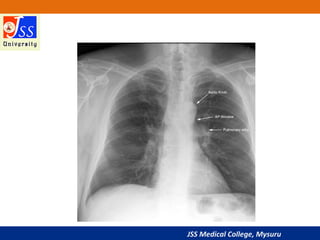

JSS Medical College, Mysuru

Mediastinum